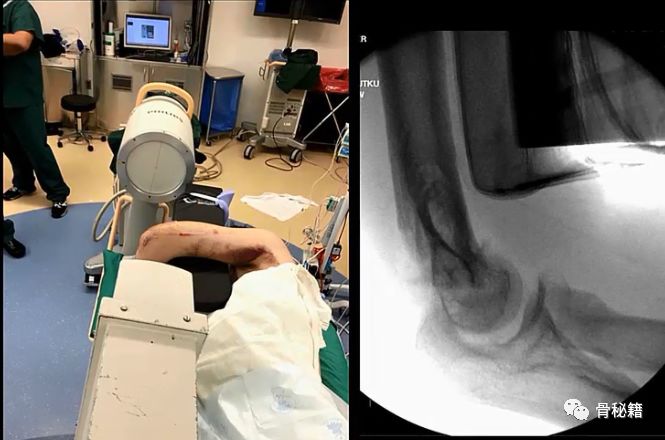

术中透视及体位,最常用的侧卧,如下图,

该体位下的透视,正位

侧位

铺单后的体位图